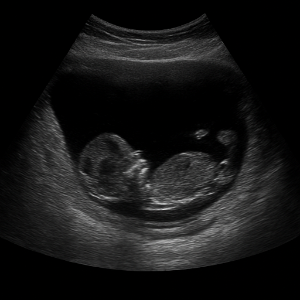

복부초음파는 우리 눈에 보이지 않는 높은 주파수의 소리(초음파)를 배 위에 대고 보내서, 몸속 장기와 혈관 구조를 실시간으로 영상으로 보는 검사입니다. 이 검사는 방사선을 사용하지 않고 통증이나 위험이 거의 없어, 안전하게 여러 번 반복할 수 있어요 .

초음파 기기에는 ‘탐촉자(transducer)’라는 작은 기계가 있는데, 이 기기가 전기 신호로 초음파를 만들어 몸속으로 보내요. 이때 사용하는 주파수는 사람이 들을 수 없는 높은 소리, 보통 2~5MHz 정도예요 .

초음파가 배 안 장기나 조직에 부딪히면 일부는 반사되어 돌아오고, 이 반사파를 탐촉자가 받아 전기 신호로 바꿔요. 컴퓨터가 이 신호를 이용해서 화면에 영상으로 보여줍니다 .

영상이 만들어지는 원리는 시간(반사파가 돌아오는 속도)과 강도(얼마나 세게 반사되었는지)를 컴퓨터가 계산해 이미지의 위치와 밝기를 결정하는 방식이에요. 깊이가 깊을수록 반사되는 시간도 길어지고, 반사파가 세면 화면에서 밝게 나타나요 .

임산부나 어린이도 검사 가능한가요?

네, 복부초음파는 방사선을 안 쓰고 안전하게 장기를 들여다보는 방법이어서 임산부나 태아, 그리고 어린이까지 모두 받을 수 있어요 . 특히, 산과 초음파(태아 초음파)는 매우 일반적이며 안전한 검사로 자리 잡았어요 .